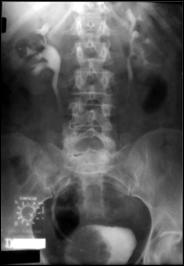

4.1. Radiografia renovezicala simpla si UIV raman examenele de baza pentru diagnosticul etiologic al oricarui pacient cu hematurie. Tumorile vezicale au drept semn radiologic cardinal imaginea lacunara pe cistograma urografica. Tumorile infiltrative pot induce modificari ale supletii peretelui vezical, care devine rigid, inextensibil, retractat etc. in zonele patologice. Ureterohidronefroza sau rinichiul mut sunt rezultatele invaziei si obstructiei ureterelor intramurale induse de tumorile solide, infiltrative (Fig.27,28,29).

a. b. c. d.

Figura 33. a) Imagine lacunara voluminoasa, ocupand

hemivezica dreapta; rinichi drept mut UIV; b) Imagine lacunara in hemivezica

dreapta; c) Rigiditate la

nivelul hemivezicii drepte; d) Cistouretrografie intramictionala

demonstrand imagine lacunara in hemivezica stanga.